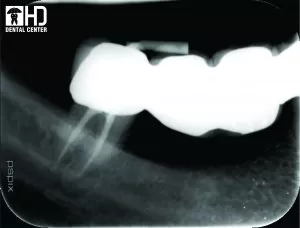

4/ Chữa tủy răng cửa hàm dưới

Đây là những răng cửa dưới có vị trí lệch ngoài, chỉ định lấy tủy để làm răng sứ thẩm mỹ. Ca chữa tủy răng cửa này được điều trị bằng trâm Hyflex.

Tât cả các trường hợp trên được điều trị tại Kubet - Ku Casino, hoàn tất chỉ trong một lần hẹn và không gây đau. Có thể nói, việc sử dụng trâm xoay Ni-Ti đã giúp chúng tôi rút ngắn thời gian điều trị, nâng cao chất lượng và hiệu quả của điều trị tủy răng, mang lại sự hài lòng và tin tưởng cho bệnh nhân.